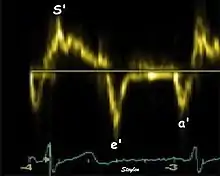

Spectral tissue velocity curves from the mitral annulus at the septal (left) and lateral (right) points. The curves show multiple heartbeats.

Single spectral tissue velocity curve from the mitral annulus. The curve shows velocities towards the probe (positive velocity) in systole, and away from the probe (negative velocities) in diastole. The most useful measures are the peak velocities, in systole S' and in early diastole (e') and late diastole during atrial contraction (a').

Annular velocities summarize the longitudinal contraction of the ventricle during systole, and elongation during diastole. Peak velocities are commonly used.